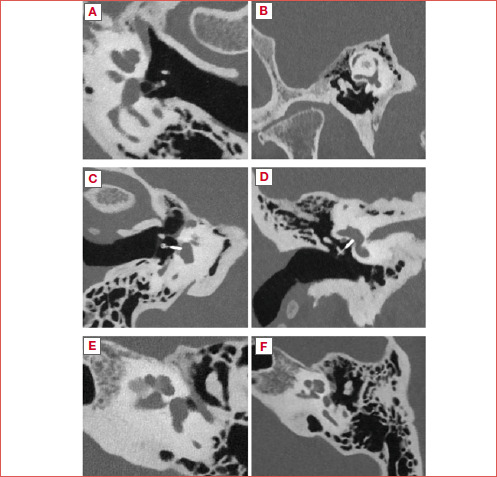

Abstract Image